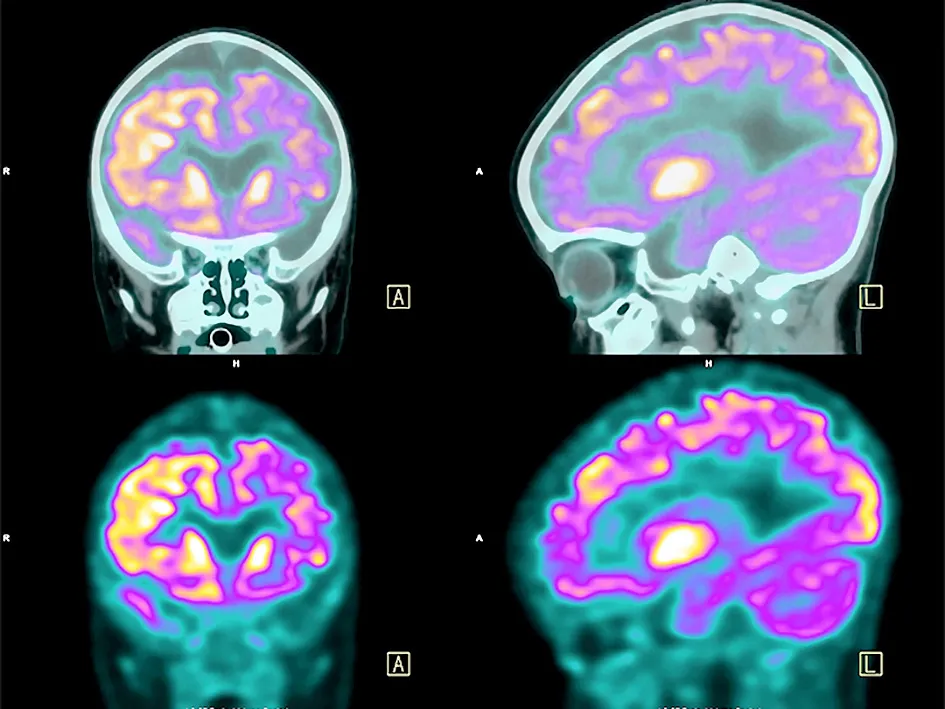

Kết quả nghiên cứu đăng trên tạp chí Brain, một tạp chí học thuật quốc tế ở lĩnh vực y học não bộ, ngày 21-1 cho biết, nhóm nghiên cứu thuộc Trường Đại học Quốc gia Seoul, Hàn Quốc, đã phát triển một công nghệ có thể chẩn đoán mức độ suy giảm trí nhớ chỉ bằng xét nghiệm máu.

Công nghệ này đưa ra chẩn đoán về sự tích tụ trong não của protein Tau, một tác nhân chính dẫn tới bệnh Alzheimer. Khi lượng protein Tau trong máu càng cao thì protein Tau tích tụ trong não càng lớn.

Nếu công nghệ này được đưa vào áp dụng thì chỉ cần xét nghiệm máu đơn giản là có thể chẩn đoán chính xác về diễn tiến của bệnh Alzheimer, góp phần giảm mạnh chi phí chẩn đoán…